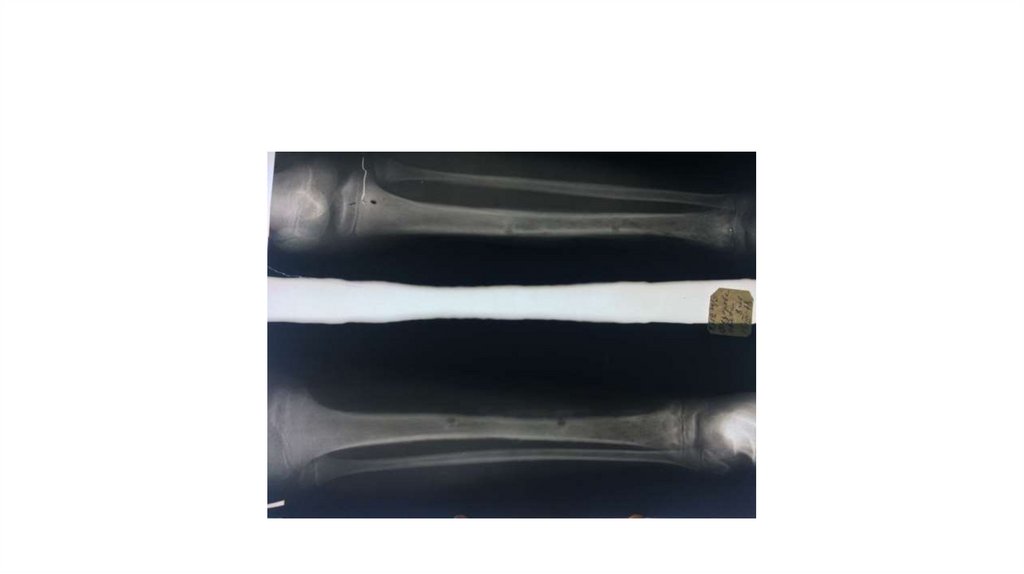

Воспалительные заболевания опорнодвигательного аппарата

«Воспалительные

заболевания опорнодвигательного аппарата»